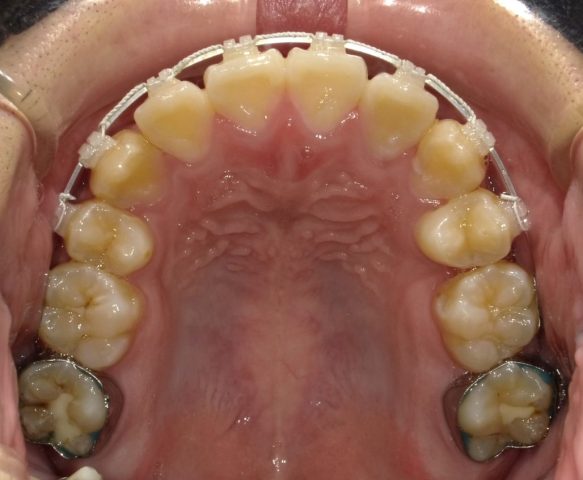

【上顎咬合面観】

2023年1月